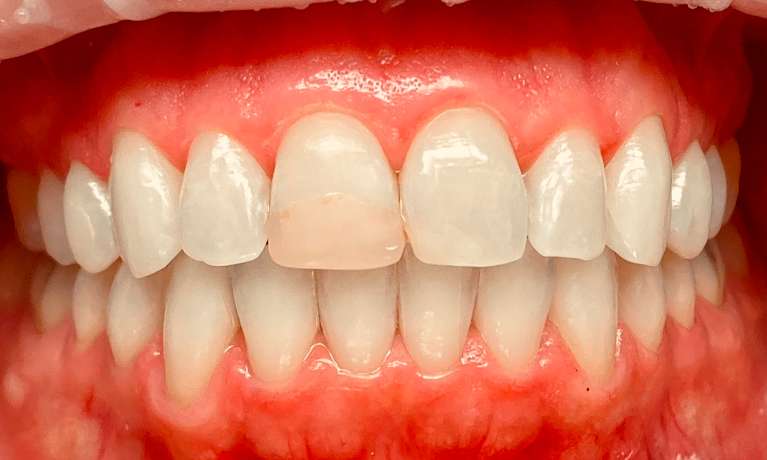

She came to us with a deep bite due to her lower front teeth sitting too high and her two front teeth pushed forward. Using Invisalign, we moved her lower front teeth down into their proper position and pulled the two front teeth back into place. She also needed a deep cleaning to removed deep buildup and restore her gum health. The results are beautiful and healthy!